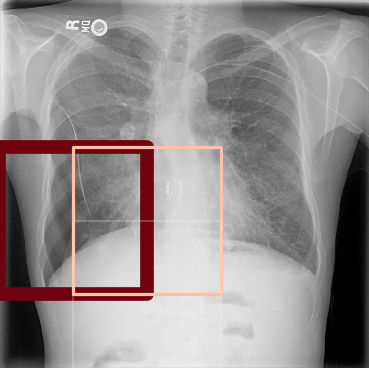

The pre-trained ResNet-50 was also employed as the patch-level classifier within the MIL approach. We chose the binary cross-entropy between the maximum patch score and the image-level label as the loss function. The batch size was selected as the number of patches per image. We trained with an initial LR of for 30 epochs and achieved an average AUC of 0.930.01 using this method. High patch scores (indicated by thicker red frames, cf. Fig. 5(c)) give a hint on the location of the pneumothorax.

As pixel-level ground truth annotations were available only for a subset of the images, 871 images in total were used for training the FCN for 400 epochs. As a loss function, a weighted cross entropy (25.0 for pneumothorax pixels and 0.5 for non-pneumothorax pixels in order to account for the smaller size of pneumothorax regions) was employed at pixel-level with an initial LR of . With an average AUC of 0.920.02, the overall performance of this method is worse than the CNN and MIL. On the other hand, the FCN generates pixel-level probabilities (cf. Fig. 5(d)), which indicate the location of the pneumothorax. The average Dice coefficient for positively classified cases is .